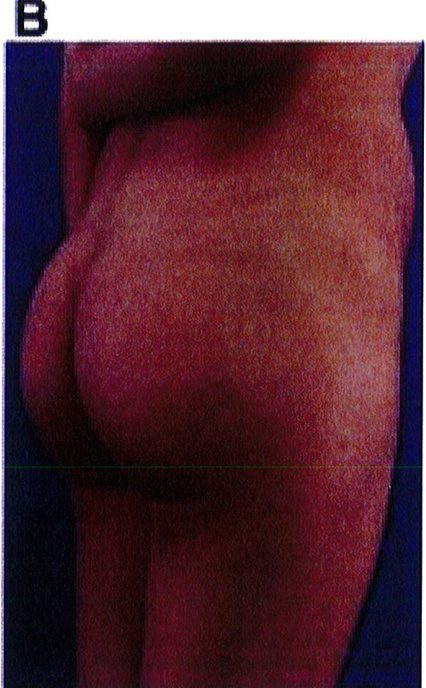

Hình. 20. (A) Hình anh trước và (B) và sau phẫu thuật làm đầy mông của bệnh nhân có vùng mông tương đối đầy đặn. Bệnh nhân được đặt khối implant dưới cân thể tích 330 mL ở hai bên.

THỜI GIAN HỒI PHỤC SAU MỔ

Bệnh nhân 30 tuổi mong muốn cải thiện hình dáng vòng ba, mặc dù vòng mông đã tương đối đây đặn. Bác sĩ sau khi đánh giá đã đưa ra quyết định hút mỡ eo và làm đầy mông bằng implant. Hai khối implant microtextured (vi nhám) thể tích 330 mL được đặt cân đối ở hai bên. Bệnh nhân sau phẫu thuật xuất hiện bục một phần vết mổ (dài khoảng 2cm) ở hai bên nhưng không sâu và đã điều trị kịp thời bằng dung dịch sát khuẩn, kháng sinh tại chỗ và toàn thân. Vết mổ liền lại tốt (Hình 20).